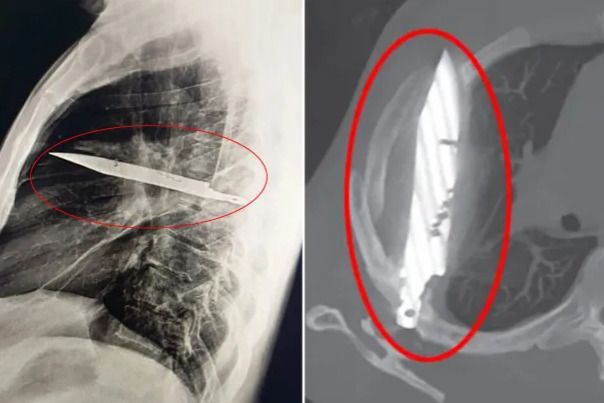

8년간 가슴 통증에 시달려온 남성의 흉부 엑스레이 사진. 흉부 중앙에거대한 칼이 꽂혀 있는 모습이 보인다. [더선 캡처]

가슴 통증의 원인을 진단하기 위해 검사하던 의료진은 흉부 엑스레이 사진을 보고 큰 충격을 받았다. A씨의 흉부 중앙에 커다란 칼이 꽂혀 있었기 때문이다.